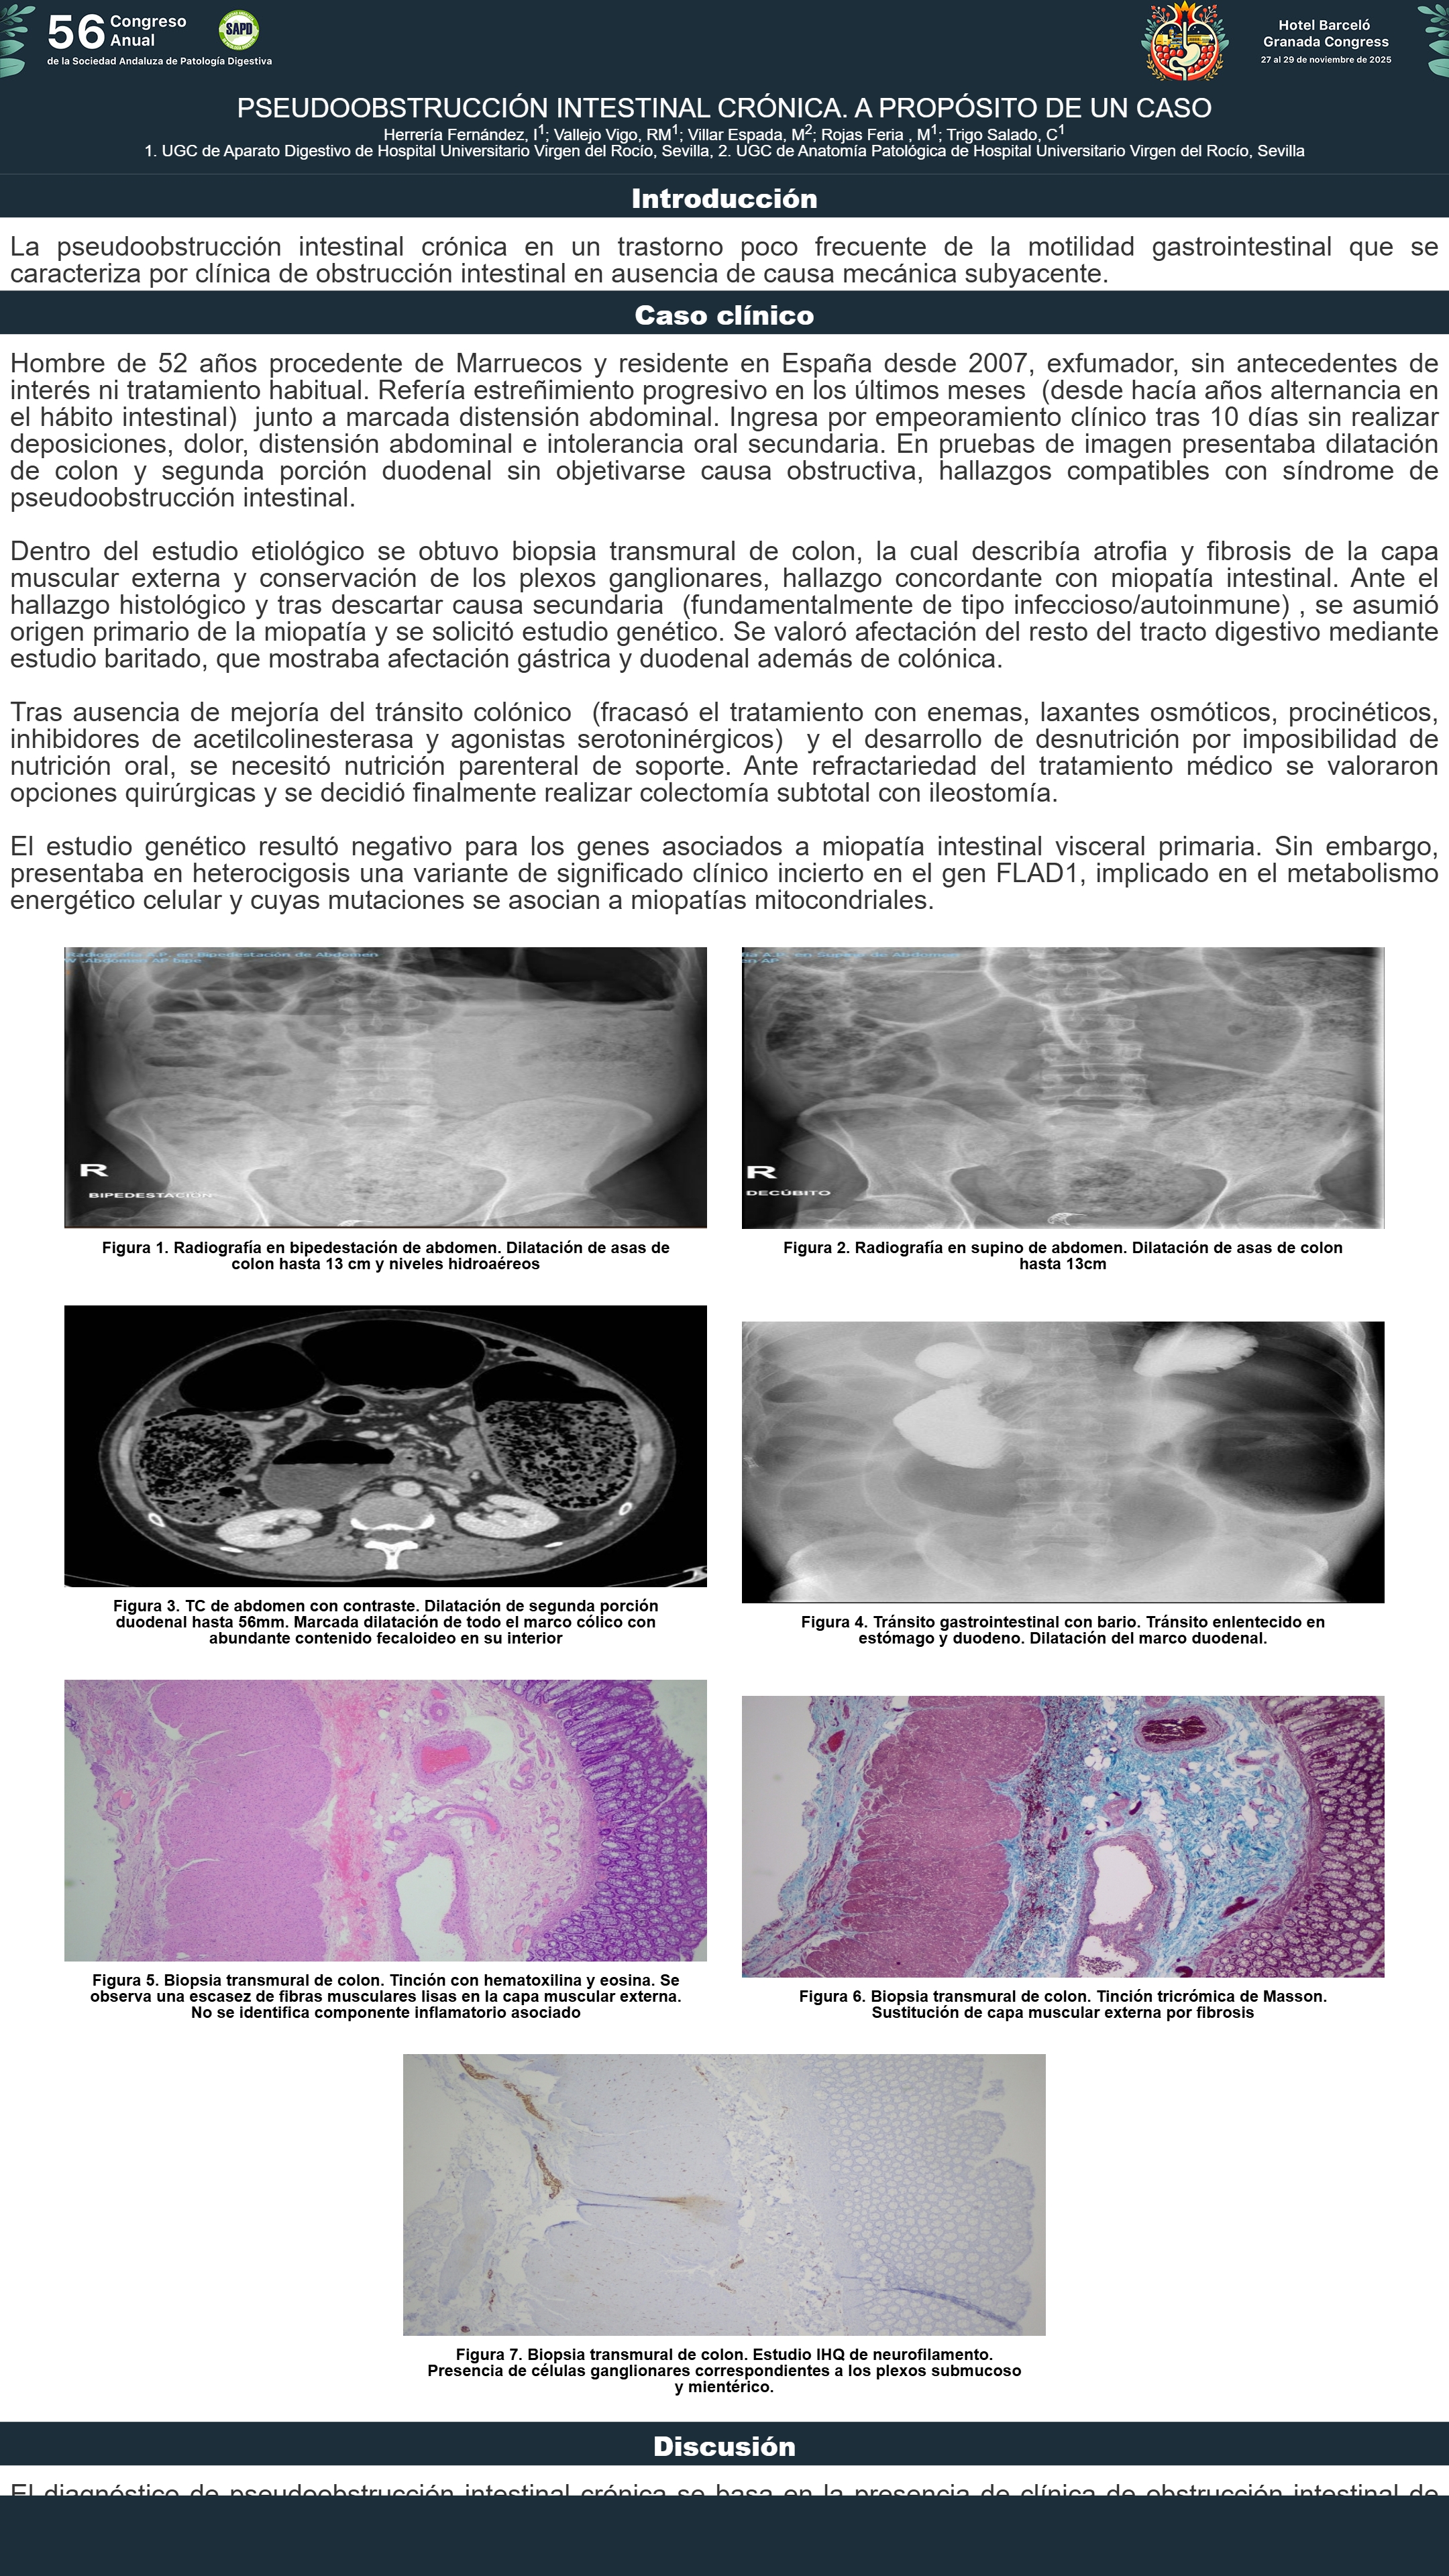

[CP-099] PSEUDOOBSTRUCCIÓN INTESTINAL CRÓNICA. A PROPÓSITO DE UN CASO